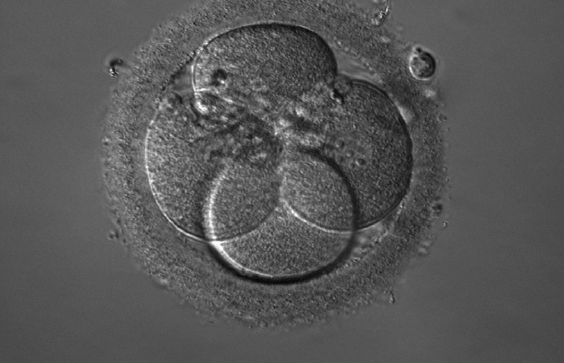

(4)胚胎观察:成功受精後,胚胎學家會在接下來的數日中監測胚胎發育情況。此外,胚胎也會接受形態學評估,並且只有評級較高的胚胎才會被選擇進行植入。霍夫曼調制對比顯微鏡HMC是在體外生殖(ART)中使用倒置顯微鏡時最廣泛應用的對比技術,因為它在解析度與對比度之間提供了良好的折衷。此對比技術常規用於 ICSI 觀察和胚胎質量評估。HMC 不使用分光棱镜,兩個偏振片光學上安裝在樣品之前;因此,HMC 可以與雙折射樣品及塑料培養皿等材料結合使用。ZEISS 改良版 HMC(iHMC)提供清晰的浮雕對比,甚至能顯示細胞核中的最細微結構、核形狀以及核仁。

spermimage

圖 4:使用 iHMC 獲得的胚胎影像。